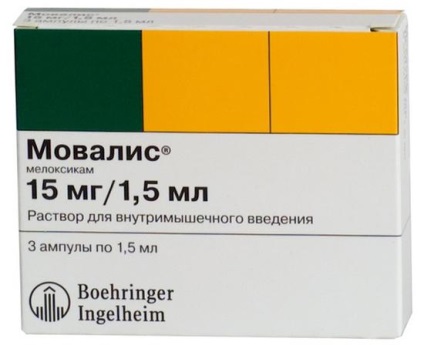

- Viselése ortopédiai termékek és a különleges párnák.

- Drug hatások. Ahhoz, hogy távolítsa el görcs relaxánsok látható. Ezek közé tartoznak, többek között különösen gyógyszerek, mint a „baklofen”, „Sirdalud”, „Mydocalm”. NSAID-ok ajánlott, mint amelyek képesek eltávolítani a fájdalmat. Közülük gyakran írnak ilyen gyógyszereket, mint „Ibuprofen”, „Voltaren”, „movalis”.

- Helyi érzéstelenítők injekciót. Bizonyos esetekben, együtt alkalmazott kortikoszteroidok. Az injekciók hozzájárul szakítsa patológiai impulzusokat kiváltó pont.